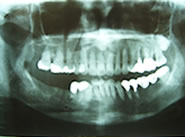

下顎右側の臼歯2本がありません

初診時のX線像です

2本のインプラントを埋入しました

手術後のX線像です

2本の白いセラミック冠が入りました

入れ歯でなく自分の歯と同じように噛めるようになりました

リコール時のX線像です